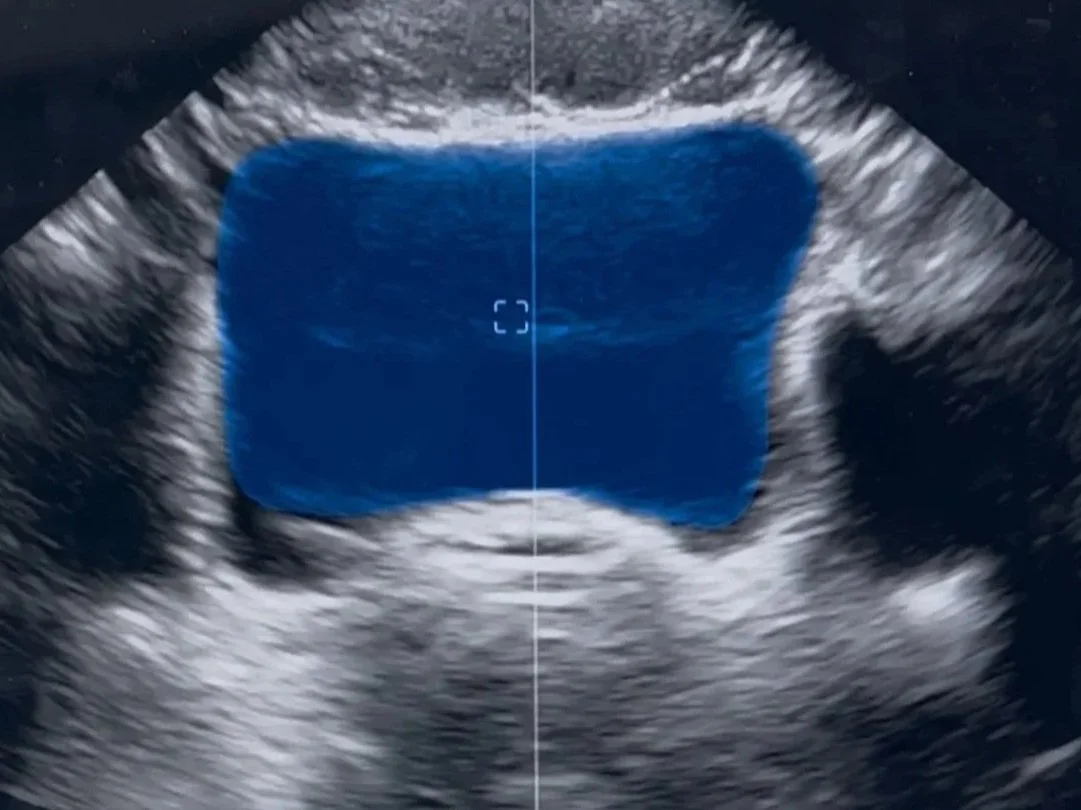

Discover how pelvic floor physical therapists use real-time ultrasound imaging to assess, train, and empower patients. Learn the benefits of ultrasound for pelvic floor rehab, biofeedback, and improved treatment outcomes.